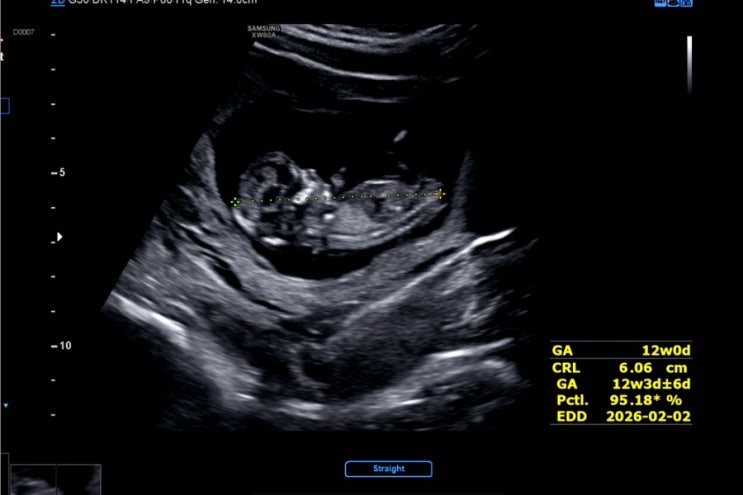

[임신일기] 25.07.24.|12주 0일|출혈 | 전치태반 | 1차 기형검사 | 유산방지주사

지금 생각해도 아찔한 가장 큰 이벤트가 있었던 7.24 드디어 안정기 진입이라며 좋아했던 전날 밤과 다르게...